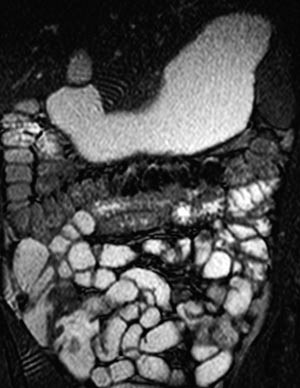

MR av tynntarm med oral kontrast

Pasienten drikker en væskeløsning med et tilsetningsstoff som hindrer absorpsjon og ev. trekker væske ut i tarmlumen. Det er prøvd mange ulike tilsetningsstoffer (7) – (13). Løsningen inntas jevnt fordelt i timen før undersøkelsen. Deretter blir den gjennomført med samme sekvenser som ved MR-undersøkelse av tynntarm med sonde.

Vår erfaring med MR av tynntarm med oral kontrast er at metoden gir en god utvidelse av ileum. Bulbus duodeni er også ofte væskefylt, men det er vanskeligere å få resten av duodenum og proksimale jejunum optimalt utvidet (fig 3). En annen ulempe med MR av tynntarm med oral kontrast er ventrikkelretensjon (fig 4). Dette hemmer væskefylling av tarmen, og pasientene kan bli kvalme.